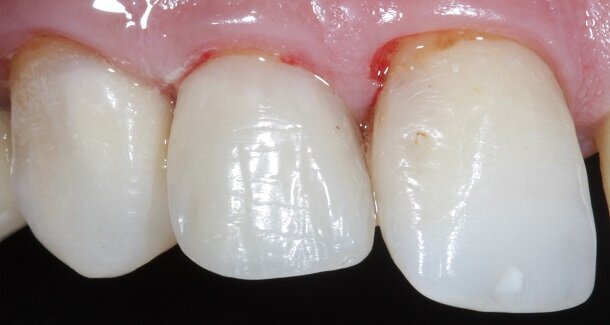

The figures show the clinical work flow involved. In the 1st appointment Oral prophylaxis, oral hygiene instructions were followed by an impression that was sent to the lab for a wax up [Fig 3 and 4]. In the subsequent appointments, Endodontic treatment was followed by Intra and extra coronal office bleaching using the Pola office bleaching kit. After two weeks, the shade stabilised post bleaching. Shade selection, rubber dam isolation and preparation was done on both the teeth to receive Direct composite veneers so as to close the midline diastema as well as correct the fractured teeth and the slight mal-alignment. Controlled Body Thickness (CBT) technique of layering was used with 3M Z350XT shades - Dentin shades A3, A2 and Enamel shades A2, clear translucent [Figures 5 to 11]. This was followed by the Finishing and polishing protocol as described in the figures.

Fig 12- Gross finishing for the outline of the tooth was achieved using Red ring (composite finishing) tapered rounded bur. Almost 80% of the finishing can be done using this bur. It also helps in creating surface macro and micro anatomical variations. For better control, this bur can be used on a contra-angled hand-piece along with a convertor.

Fig 22, 23 and 24 - In the post-rehydration follow-up appointment, the patient requested us to reduce the lengths of the central incisors slightly, and we reduced it by 0.5mm till he was satisfied.